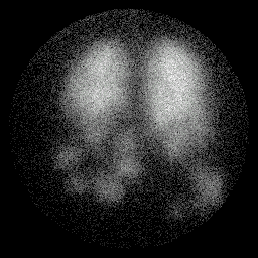

Example of COAD

Posterior Perfusion Posterior Ventilation

match_perf1.gif (19089 bytes) match_vent1.gif (20226 bytes)